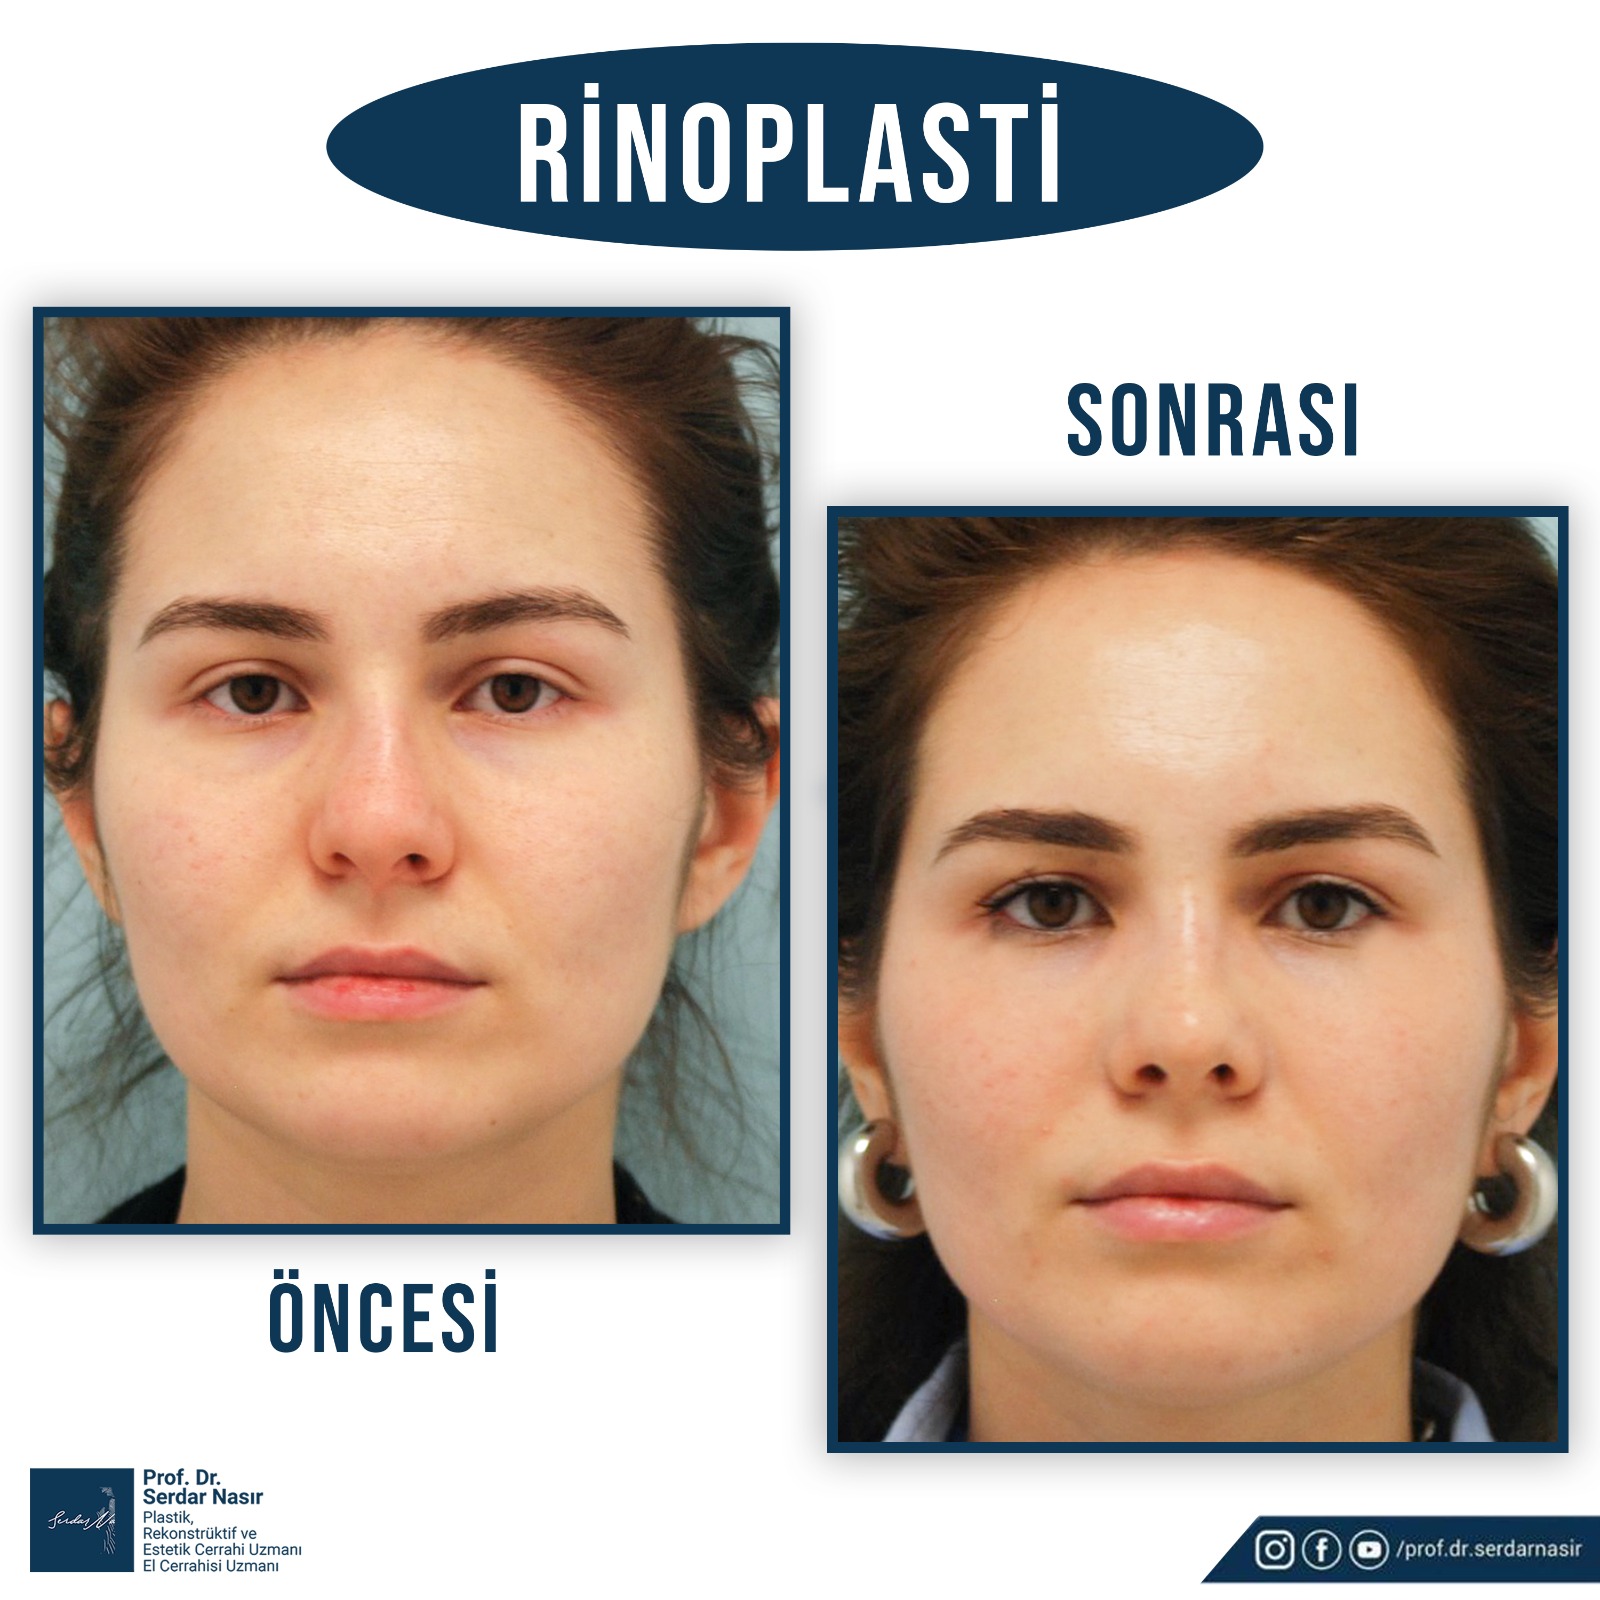

Estetik burun ameliyatı bana göre plastik cerrahinin en zor ameliyatlarından biridir. Çünkü burunda estetik olarak güzel bir sonuç elde etmeye çalışırken aynı zamanda fonksiyonel sonuçta yani hastanın nefes alıp vermesininde bozulmaması ve hatta sorun varsa düzeltilmesi gereklidir. Bu nedenle oldukça dikkatli yapılması gereken ameliyatlardır. Şu da bir gerçektir ki en çok revizyon dediğimiz ilk ameliyattan sonra tekrar bazı küçük deformitelerin veya hoşa gitmen bazı ayrıntıların düzeltilmesinin yapıldığı ikinci ve bazen üçüncü ameliyatlar en çok bu grupta saptanmaktadır. Bu nedenle özellikle ilk ameliyatın başarılı şekilde yapılması bu revizyon olasılığını azaltacaktır. Yine de estetik burun ameliyatı olmayı planlayan bir kişi her zaman için bir revizyon olasılığını akılda tutmasını öneririm.

Burun ameliyatları kapalı veya açık olarak iki teknikle yapılmaktadır. Plastik Cerrahlar hem kendi deneyimleri hemde hastanın ihtiyacına göre bu tekniklerden birini seçmektedir.

Kişisel tecrübeme gelince ameliyat sonrası şişliklerin daha az olması, dokuları daha az travmatize etmesi gibi düşüncelerle ilk planda kapalı tekniği tercih etmekteyim. Ancak hastanın burun deformitesi özellikle burun ucuna yönelik ağırlıktaysa veya çok detaylı bir cerrahi girişim yapılacaksa açık tekniği tercih etmekteyim. Ancak tecrübelerime göre kapalı teknik ile açık tekniğe gerek kalmadan bir çok hastanın sorunu çözülebilmektedir.